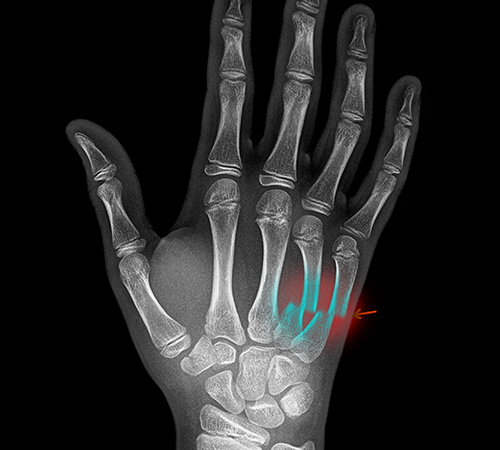

류마티스관절염

• 정상

• 류마티스관절염

• 류마티스관절염 진단

X-선 검사에서 발견되는 뼈의 침식 징후